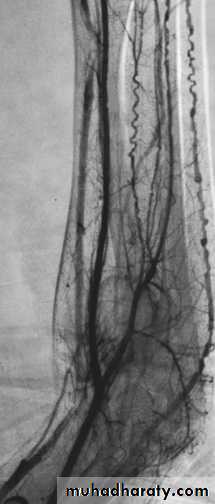

Buerger's disease